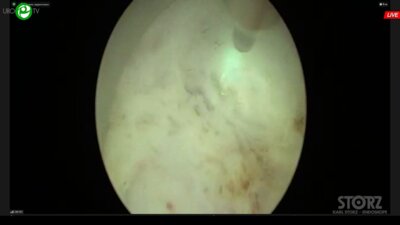

Сорокин Николай Иванович

д.м.н., профессор, руководитель урологической службы МНОЦ МГУ, ведущий научный сотрудник ФФМ МГУ им М.В. Ломоносова